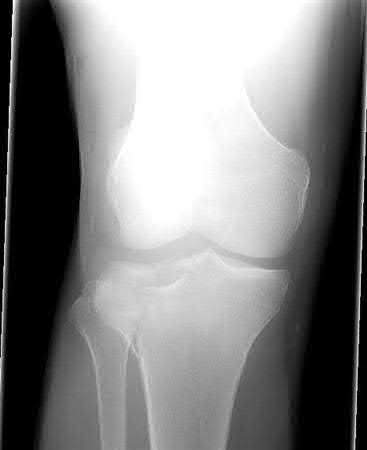

Buttress plating is most appropriate in which of the following clinical situations?

There are 4 main types of plating techniques: 1. Bridging 2. Neutralization 3. Dynamic Compression 4. Buttress plating. Plates can utilize locking or non-locking screws.

Buttress plating is appropriate for a Shatzker Type I (see illustration C), as it can prevent collapse and axial deformity from shear or bending forces.

Figure B demonstrates an isolated medial femoral condyle fracture. Lateral locked plating is not an appropriate technique for this fracture.

The fracture shown in Figure B is an AO B type (partial articular fracture). This fracture is best treated with open reduction internal fixation through a medial approach, with lag screw and buttress plate fixation.

Figures A, C, D and E show supracondylar distal femur fractures that can be treated with ORIF with a fixed-angle device such as lateral locked plating.